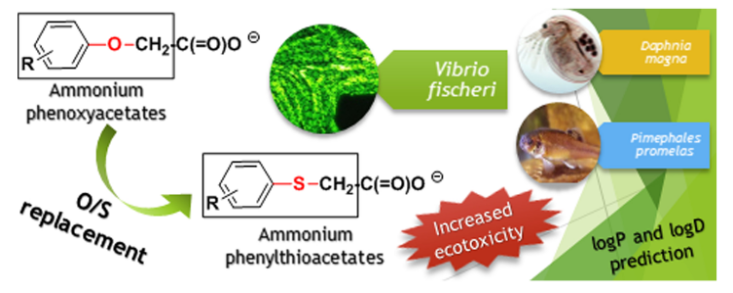

4.3.5 成药性预测

4.3.5 成药性预测

在药物发现和开发的过程中,成药性预测(Drug-likeness prediction)是一个重要的步骤。成药性是指一种化合物是否具有成为有效、安全、口服生物利用度高的药物的潜力。这通常涉及到化合物的各种物理化学属性,如溶解度、透膜性、稳定性、毒性等。

在分子动力学模拟中,可以通过模拟化合物在生物体内的行为,包括与生物分子的相互作用、在体内的分布、代谢和排泄等过程,来预测化合物的成药性。

此外,还有一些经验规则和计算模型可用于成药性预测,如Lipinski的“五规则”(Lipinski's Rule of Five)和Veber规则等。这些规则基于已知药物的物理化学性质,为新的药物分子设计提供了指导。

总的来说,成药性预测是一个复杂的过程,需要考虑多种因素,并且通常需要结合实验数据进行验证。